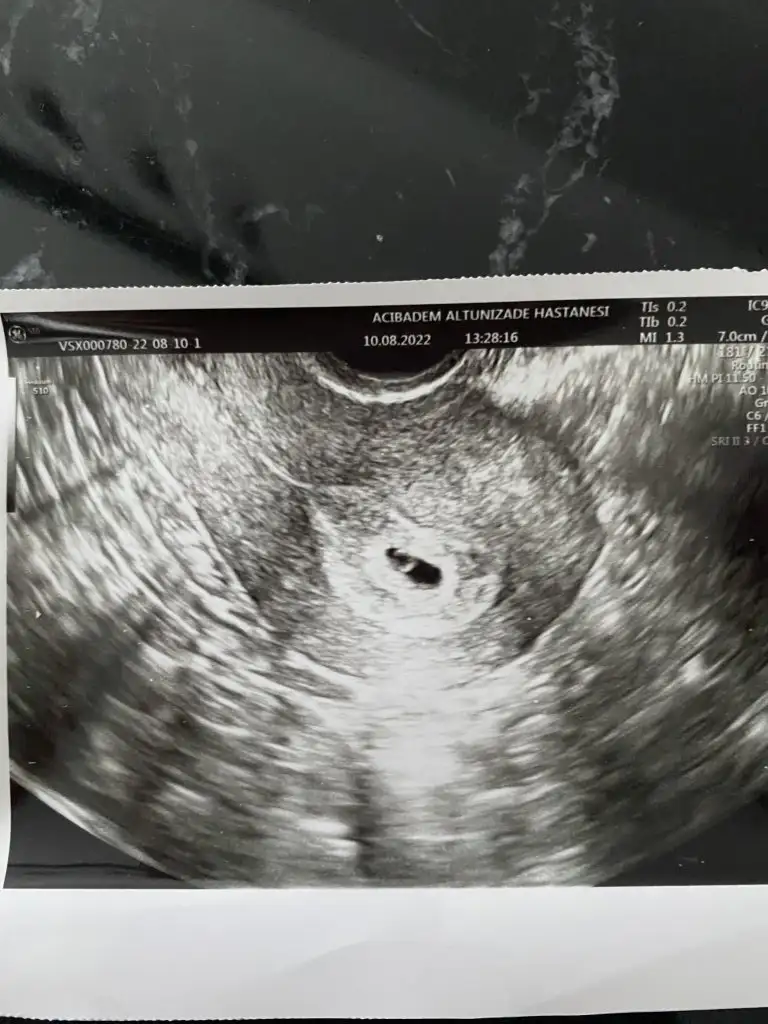

11+3 ten selamlar

Hepimizin bebeği sağlıkla gelsin. İster kız ister erkek farketmiyordu bizim için. Çünkü ilk bebeğimiz ve 2 düşük sonrasında tüp bebekte tek embriyo elde etmiştik, onu gönderdik rahime ve tutunmuş. İnanılır gibi değil gerçekten. Havalara uçuyoruz şu anda evde